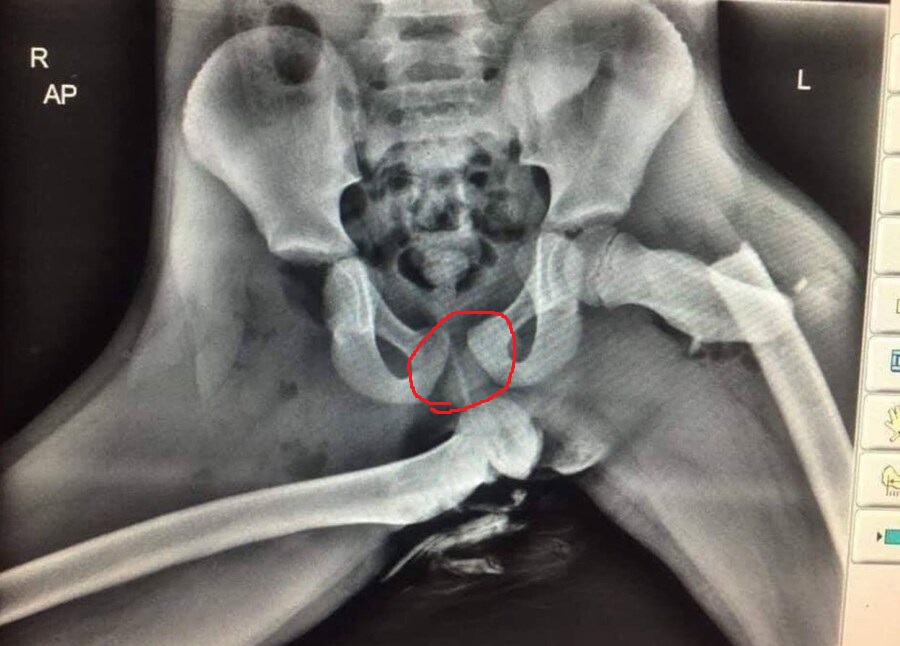

저거 꼬추임?

베네치아의 약물상인

뼈가 살 뚫고 나와서 근육이랑 가죽이 너덜너덜 덜렁덜렁 하는 거. 골반 형태 보면 알겠지만 저거 엑스레이 찍힌 사람은 여성임. | 25.12.27 01:43 | | |

환상의구루텐

(IP보기클릭)121.173.***.***

남자 골반은 애가 나올 공간이 필요없기 때문에 골반 가운데 구멍이 저 사진보다 작음. | 25.12.27 01:47 | | |

각도는 뭐... 애초에 골반도 부러지고 꺾인 상황이라...ㅋ | 25.12.27 01:50 | | |

그러니까 네가 '길다'고 보는 구조가 원래 각도가 아니라 골반에 대퇴골 끼우는 부분이 양쪽 다 부러져서 아래로 기울어서 길어 보이는 거. 그리고 실루엣 자세히 보면 오른쪽으로 심하게 밀려난 여성기 실루엣도 보임. | 25.12.27 01:54 | | |

그러니까 네 동그라미에 닿은 뼈가 골반에 제대로 붙어 있으면 네 말이 맞는데, 그게 원래 있어야 할 자리가 거기가 아니잖아.ㅋ 둘 다 골반에서 부러져서 이탈한 상태라 그 자리로 보는 건 의미가 없어. | 25.12.27 01:59 | | |